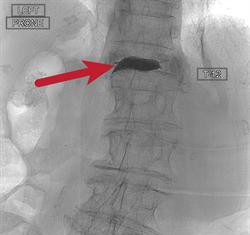

A los 99 años, una mujer recupera movilidad de la columna...

Una mujer de 99 años de edad, ha vuelto a su rutina diaria después de tres doctores repararlas fracturas por compresión por separado en la columna tres veces en un mes. Especialistas de la Universidad de Rochester Medical...